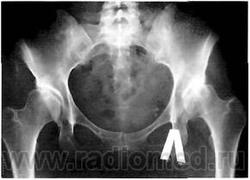

Рис. 7. Рентгенограмма больной с двусторонней дисплазией тазобедренных суставов. Кранеолатеральная инклинация вертлужных впадин, недопокрытие головок бедренных костей. Начальные признаки коксартроза: субхоидральный склероз крыши вертлужной впадины, незначительное сужение суставной щели.

При деформирующем артрозе, развившемся на почве дисплазии тазобедренного сустава, оценивают следующие рентгенологические показатели: характеризующие вертлужную впадину: состояние крыши и самой впадины; угол наклона плоскости входа во впадину (УВН); относящиеся к проксимальному отделу бедренной кости (шеечно-диафизарный угол); признаки соотношения вертлужной впадины и головки бедренной кости: а) угол Виберга; б) линия Шентона; в) угол вертикального соответствия; г) степень покрытия головки бедренной кости.

Рентгенологическая картина диспластического коксартроза зависит от выраженности анатомических изменений (различают вывих, подвывих и дисплазию) и стадии заболевания. На ранних стадиях превалируют признаки анатомических нарушений в суставе: вертлужная впадина обычно плоская со скошенной крышей (т.н. краниолатеральная инклинация крыши вертлужной впадины), УВН больше нормы (рис. 7).

Ацетабулярная дисплазия чаще всего сочетается с coxa valga и избыточной антеверсией шейки бедренной кости, что приводит к перегрузке переднего отдела сустава, растяжению капсулы. Нестабильность тазобедренного сустава определяется по уменьшенному углу Виберга (диагностическое значение имеет угол менее 20°), нарушению линии Шентона, недопокрытию головки бедренной кости. Неблагоприятное, с точки зрения биомеханики, распределение нагрузок в суставе вызывает постоянное смещение головки вверх и латерально, избыточное давление на ограниченный участок вертлужной впадины и головки бедренной кости. В результате этого, с одной стороны, происходит развитие кист на месте концентрации напряжения (как правило, это симметричные участки в головке и крыше вертлужной впадины), с другой, развиваются оссификаты на месте постоянного напряжения капсулы сустава - в области прикрепления хрящевой губы к краю вертлужной впадины и нижнего отдела головки бедренной кости и вертлужной впадины.

При дальнейшей нагрузке происходит постепенная деформация головки бедренной кости; она смещается вверх, ротируется кнаружи и приводится, что клинически соответствует развитию стойкой сгибательно-приводящей контрактуры сустава (рис. 8).